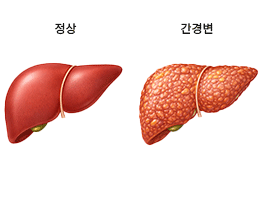

간염 (Hepatitis)

간경변 (Liver Cirrhosis)

지방간 (Fatty Liver Disease)